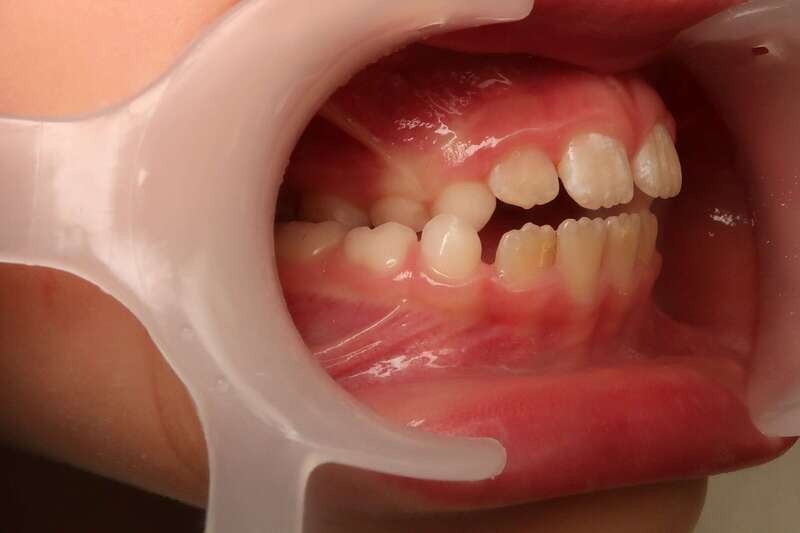

Cas n°1 traité par aligneurs (interception) - enfant

Ce cas d’interception chez un enfant de 8 ans démontre l'efficacité des aligneurs pour corriger des troubles fonctionnels précoces. Le diagnostic présentait des inversions d'articulé provoquant une déviation de la mandibule vers la gauche et un décalage des milieux.

Grâce à une coopération exemplaire et un traitement totalement indolore, l'expansion de l'arcade a permis de recentrer la mâchoire. Cette intervention a littéralement remis la croissance sur les rails, neutralisant le risque d'asymétrie faciale squelettique.

• Correction fonctionnelle : Recentrage immédiat de la mandibule et des milieux inter-incisifs.

• Prévention : Création d'un environnement favorable pour les dents définitives à venir.

• Bien-être : Approche douce respectant le confort de l'enfant.

C'est une étape fondamentale qui simplifie l'avenir orthodontique du patient tout en garantissant un développement facial harmonieux.